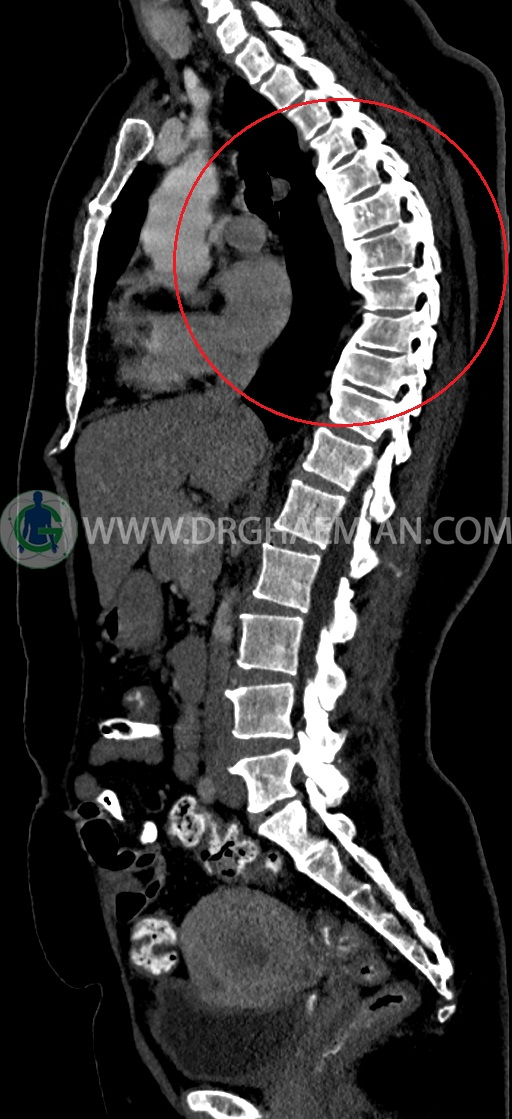

سی تی اسکن شکم و لگن یکی از روش های تصویربرداری با سی تی اسکن است. این روش با استفاده از اشعات ایکس تصاویر عرضی از ناحیه شکمی و لگنی ایجاد میکند. در این کیس سی تی اسکن هیپراستوز اسکلتی ایدیوپاتیک منتشر (DISH)، فیبروم اینترامورال، هرنی سوپرا امیلیکال دیده می شود.

–Bridging osteophyte در مهره هاي توراسيک مطرح کننده DISH همراه با کيفوز مشهود است.